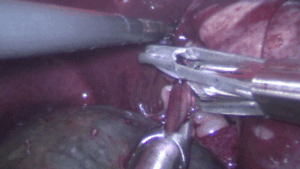

【腹腔鏡による胆嚢摘出】胆嚢粘液嚢腫

嘔吐下痢で入院しましたが、腹部超音波検査で胆嚢粘液嚢腫が発見されました。

胃腸炎の症状は改善しましたが胆嚢の炎症所見は経過観察の中で進行している様子だったため、一般状態が良いうちに摘出手術と肝臓の生検を腹腔鏡で行うことになりました。経過は良好です。